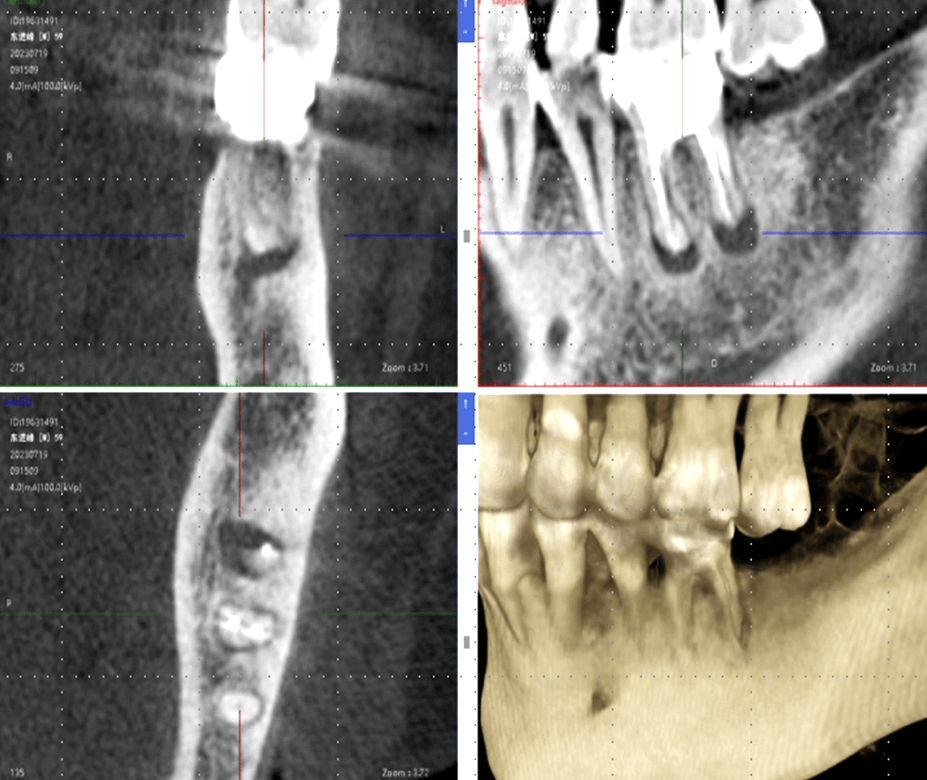

CBCT inicial + digitalização intraoral

Adaptação a diferentes dados de CBCT e digitalização intraoral; tratamento numa única visita, planeamento imediato; cirurgia no mesmo dia / prótese no mesmo dia

Exportação com um clique das principais estruturas anatómicas dentárias

Segmentação Inteligente Automática;

Extração Rápida de Informação sobre a Posição Dentária

Registo Secundário de Pontos e Nuvem

Integração precisa entre modelos virtuais e estruturas reais